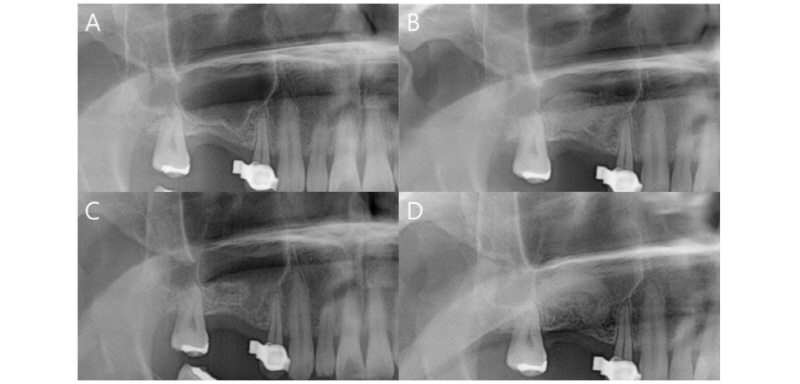

만 78세의 여성 환자가 #26 치아의 파절 원인으로, 발치 및 임플란트 위해 의뢰되었다. 특기할 만한 전신적인 병력은 없으며, #27 치아는 중증 치주염으로 인해 9개월 전 발거되었다. #27 발치 3개월 후 촬영한 방사선 사진상에서는 방사선 투과상의 발치와가 관찰되며, #26의 불완전한 근관치료 상태 관찰되었다 (Fig. 1).

#26 발거 및 소파술 시행 후 발치와 부위에 이종골 이식재(THE Graft®, Purgo, Seoul, Rep. of Korea) 이식 후 #27 무치악 치조능 부위 유경 판막 형성하여 회전시켜 발치와 부위 일차 봉합 시행하였다. 수술 4개월 후 예방적 항생제(Amoxicillin 500 mg) 복용 후, 전층 판막 거상하여 #26 임플란트 위치시킬 부위 trephine bur 이용해 조직 채득하였다. 임플란트 고정체는 tapered 형태(Luna®, Shinhung, Seoul, Rep. of Korea)의 직경 5.0 mm, 길이 10 mm 를 사용했으며, 직경 5.0까지 드릴링 후 countersinking 하였다. 식립 시 50 Ncm로 고정하였으며, 추가적으로 handwrench 사용하여 위치시켰다 (Fig. 2).

수술 당시 지대주 연결 동시에 시행하였다. 4개월간의 치유 기간 후 최종 보철물 장착하였다. 수술 이후 약 1년이 경과하였으며, 현재까지 변연골 소실이나 통증, 임플란트 동요도 없이 성공적으로 유지되고 있다.